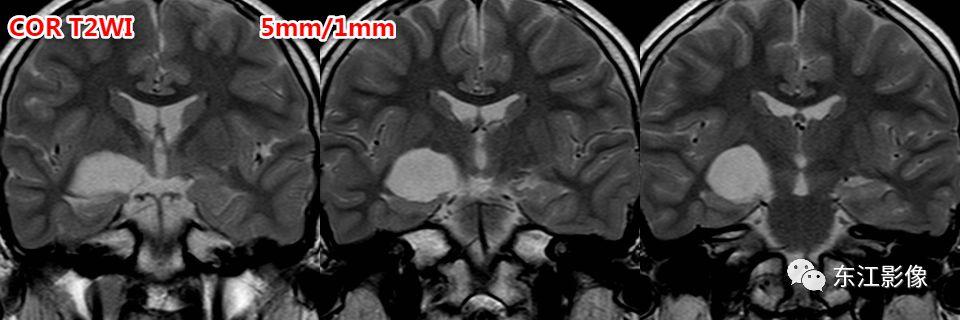

脉络膜裂囊肿

- 定位是其主要依据,冠状面、矢状面有助于区分。

- 脉络膜裂囊肿起自脉络膜裂,更容易沿脉络膜裂延伸、向下压迫海马。

- 而前穿质区扩大的血管周围间隙是起自前穿质区,较大时容易向脉络膜裂方向膨隆,因此脉络膜裂是受压变窄的,且“囊样灶”下方可见残存的“基底节区”脑实质。

脉络膜裂囊肿,与前穿质区扩大的血管周围间隙比较。

前穿质区扩大的血管周围间隙经常被误诊为脉络膜裂囊肿、腔隙性梗死灶。

信号上血管周围间隙与脉络膜裂囊肿没什么差异,形态学有一定的价值。

前穿质区是血管周围间隙最常见的部位,主体位于脑实质,层面合适时可见尖角(==》多方位观察)。

矢状或冠状薄层图像更容易显示向下突出的“残留”的脑实质!这是区分两者的重要影像证据!

脉络膜裂囊肿位于脉络膜裂,先引起脉络膜裂增宽,海马受压;压力大时,才向上压迫前穿质区脑实质。

注意,海马的压力较前穿质区脑实质小得多,所以脉络膜裂囊肿更容易压迫海马,因此主体部位不应是位于前穿质区!